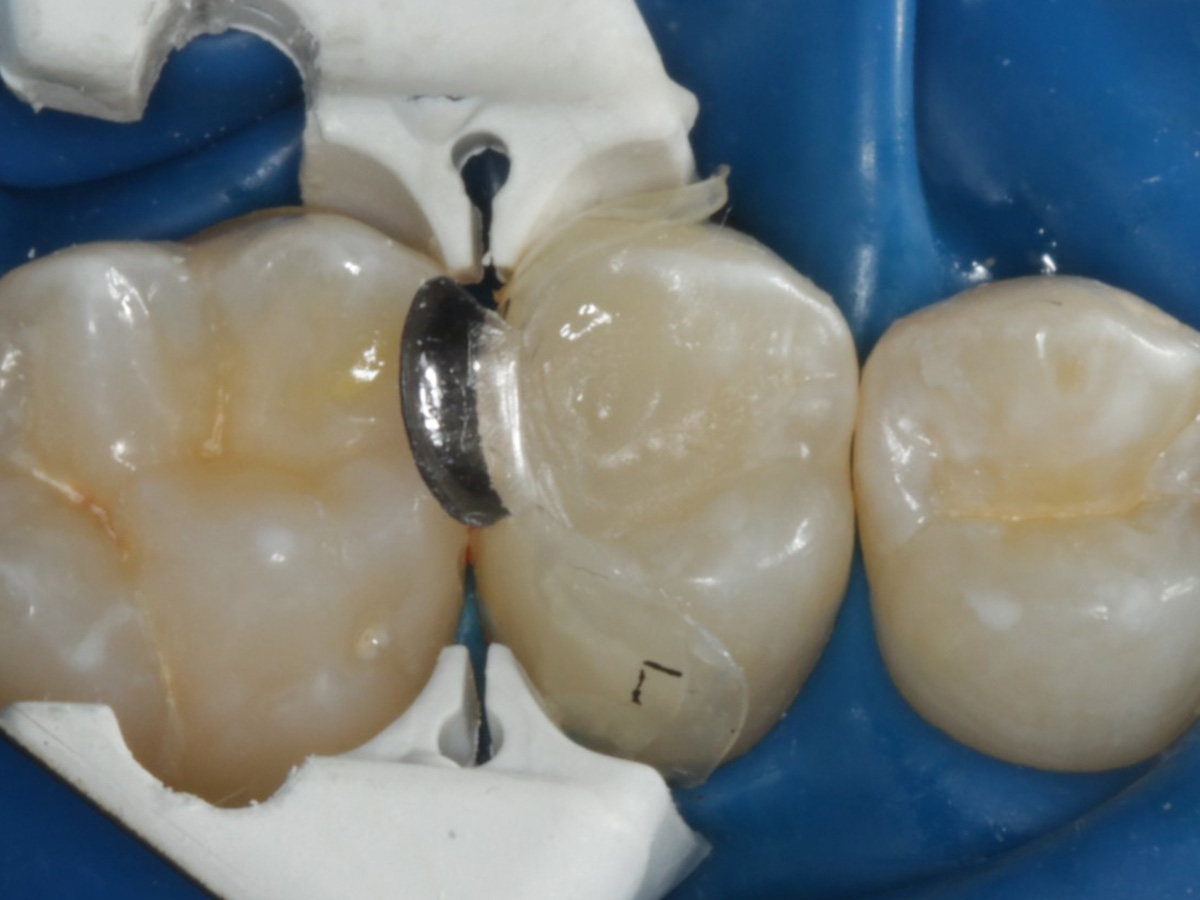

Abbildung 4

Schutz des Nachbarzahnes und des Kofferdams mit wiederverwandter Bioclear Biofit Matrize (gereinigt und sterilisiert)